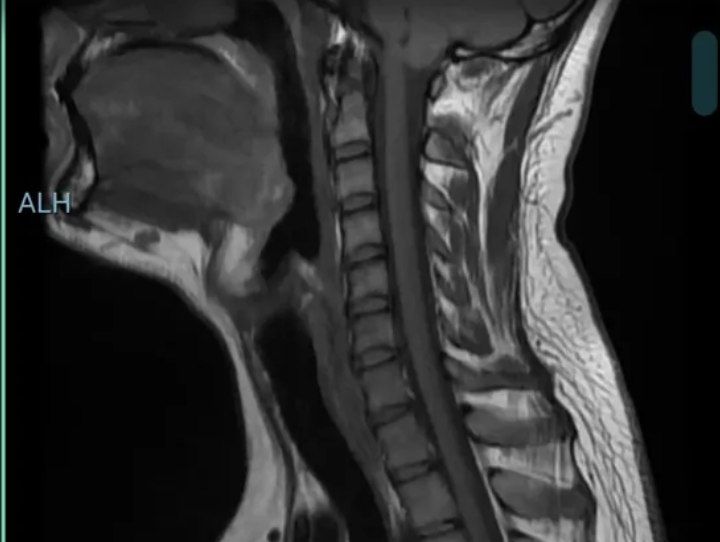

این تصویر MRI از ناحیه گردن (سرویکال اسپاین) و پایه جمجمه هست. بر اساس نگاه اولیه:

به نظر می‌رسه که توده‌ای بزرگ در ناحیه پشت حلق (نازوفارنکس یا فضای رتروفارنژیال) وجود داره که فضای پشت آناتومی طبیعی رو اشغال کرده.

این توده باعث جابه‌جایی نخاع گردنی و فشار به اون شده.

نخاع در برخی نواحی تحت فشار قرار گرفته که ممکنه علائم عصبی ایجاد کنه.

اما، تفسیر قطعی MRI فقط با مشاهده تصویر و بدون شرح حال بیمار، نشانه‌ها، و تطبیق با یافته‌های کلینیکی ممکن نیست. بهتره هر چه زودتر این تصویر رو به پزشک متخصص مغز و اعصاب یا جراح مغز و اعصاب نشون بدی.

این تصویر، یک MRI از ناحیه گردن و مغز (Cervical

به نظر می‌رسد فشردگی یا بیرون‌زدگی دیسک بین مهره‌ای در ناحیه گردن وجود دارد، که ممکن است باعث فشار روی نخاع شده باشد.

در برخی مهره‌ها، فضای دیسک کمتر از حد معمول دیده می‌شود.

نخاع در بعضی نواحی ممکن است کمی باریک به نظر برسد که می‌تونه نشونه‌ای از فشار یا آسیب عصبی